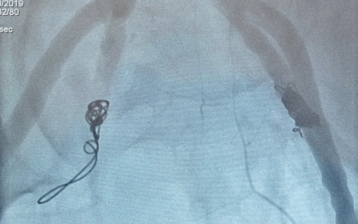

Se comunicó con el departamento de imagenología y se decidió angioembolización de arterias hipogástricas. Aunque no se evidenció fuga de contraste a ningún nivel durante la angiografía, igualmente se procedió a embolizar ambos troncos anteriores de arterias hipogástricas con partículas de PVA (partículas de alcohol polivinílico). Luego se embolizaron ambas arterias hipogástricas con coils tipo Nester (figura 3). Franca mejoría posterior, se lograron suspender los vasopresores al día siguiente, sin complicaciones vinculadas a la angioembolización. Alta de UCI al vigésimo día, se trasladó a centro de traumatología para resolución definitiva de las fracturas pélvicas. Posteriormente alta a domicilio.

Las indicaciones para angioembolización durante la angiografía incluyen extravasación de contraste, pseudoaneurisma, sección vascular, corte de relleno abrupto y vasoespasmo (figura 4). En el paciente no se evidenció ninguno de estos hallazgos, igualmente la bibliografía apoya la embolización empírica no selectiva de ambas arterias hipogástricas en pacientes que persisten en shock, fundamentando la probable existencia de hemostasis inestable de los vasos, bajo flujo por hipotensión y/o dirección selectiva del contraste4. El otro fundamento fisiopatológico que favorece la angioembolización empírica a pesar de la ausencia de fuga de contraste es que la disminución del input arterial lleva a la reducción de la presión hidrostática capilar y venular, con lo que se disminuye el sangrado por ruptura microvascular y venosa14,16.